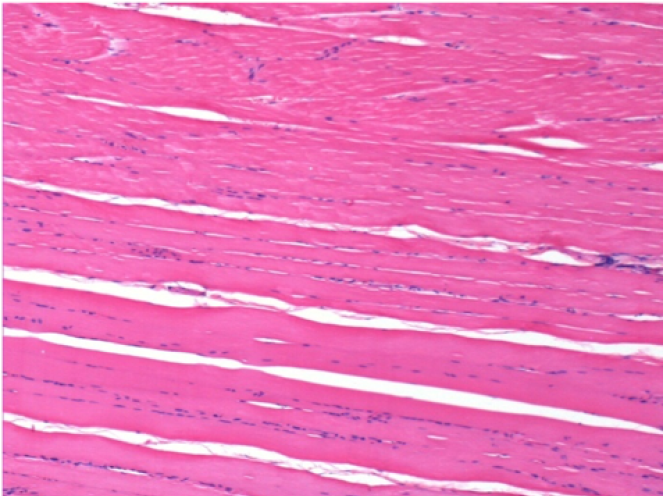

Histology

On Wistar rats

Courtesy of Lab of Pathology Department on Medicine School of Ribeirão Preto – USP

-hematoxilin-eosin

7 months (D210)after Endopeel IM Injection 0.1ml in the right pretibial muscle.

Complete Restitutio ad integrum after 7 months